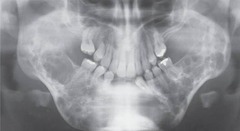

-40-60yr men>women -asymptomatic pink bulge at the incisive papillae area well circumscribed radiolucency between the maxillary central incisors -HEART SHAPED